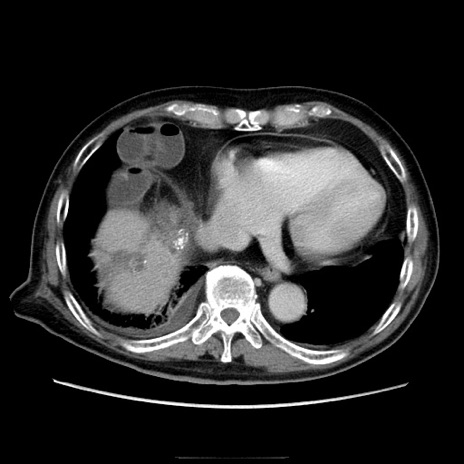

冠状断像